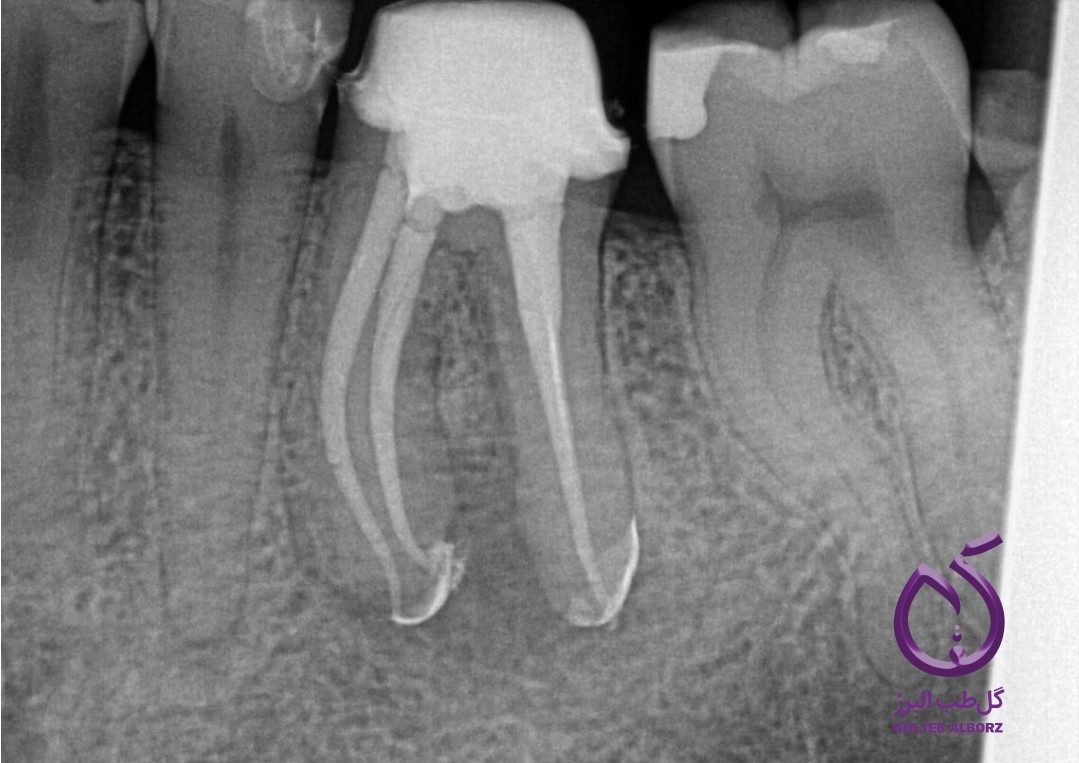

آبچوریشن سهبعدی به عنوان پر کردن و آب بندی کامل کل سیستم کانال ریشه، از جمله آناتومی پیچیده آن، در سه بعد تعریف می شود. هدف اصلی این تکنیک از بین بردن باکتری ها، جلوگیری از عفونت مجدد و تسهیل بهبود بافتهای پری آپیکال است. دستیابی به یک مهر و موم کامل بسیار مهم است، زیرا از کانال ریشه در برابر آلودگیهای خارجی محافظت می کند و محیطی مناسب برای بازسازی بافت فراهم می کند.

رادیوپاسیتی: بسیاری از سیلرهای بیوسرامیک رادیواپک هستند و امکان تجسم آسان در رادیوگرافی را فراهم میکنند. این ویژگی به پزشکان کمک می کند تا کیفیت آبچوریشن را در طول ویزیتهای بعدی ارزیابی کنند.